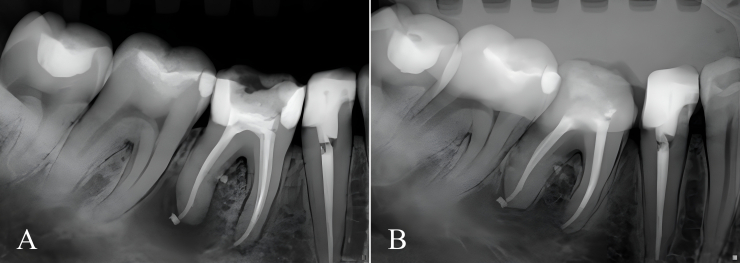

Materials and method: Fifty mandibular molars were selected and instrumented with ProDesign Logic files. First, mechanized patency was performed with a 25/0.01 instrument; if it was easily achieved, a larger diameter instrument was chosen (30/0.01, 35/0.01, or 40/0.01) that best matched the apical foramen. Then, a respective shaping file corresponding to the patency file was selected for instrumentation. Irrigation was carried out with saline solution and 2% chlorhexidine gel. A 17% EDTA solution was used for the final irrigation and agitated with the EasyClean system. A device was used to standardize the initial, final, and subsequent digital radiographic examinations for the follow-up. A 3-level scoring system was used for evaluation, in which score 1 indicated complete lesion healing, score 2 incomplete healing, and score 3 no healing.

Results: There was no significant difference between the frequencies of scores 1 and 2 assigned at the two assessment time points (p > 0.05). Complete healing (score 1) was observed in 58%, incomplete healing (score 2) in 42%, and no healing (score 3) in 0% of cases.